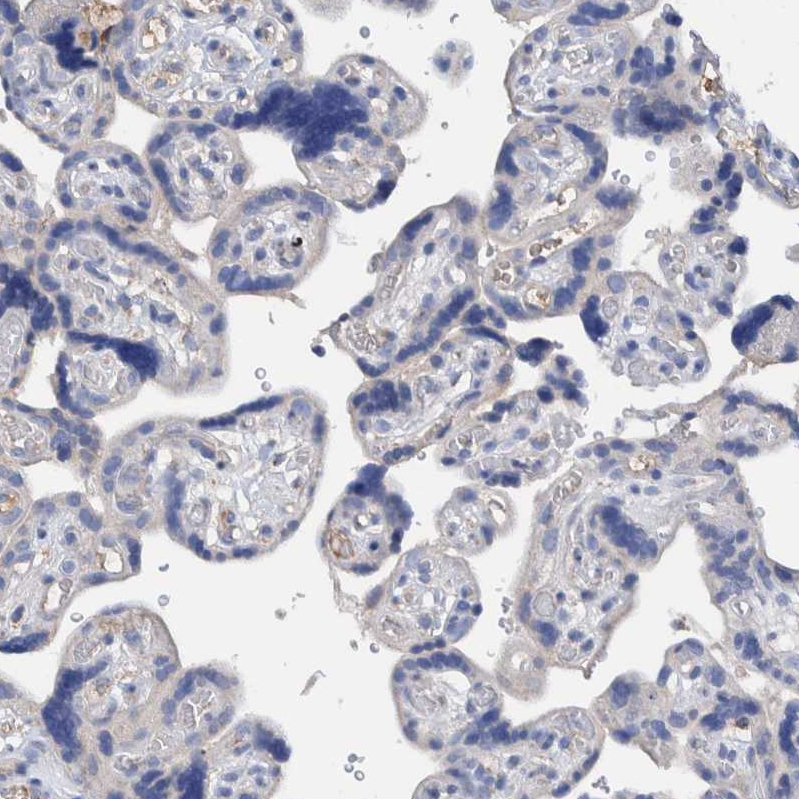

Immunohistochemistry analysis in human liver and placenta tissues using HPA023160 antibody. Corresponding DECR1 RNA-seq data are presented for the same tissues.